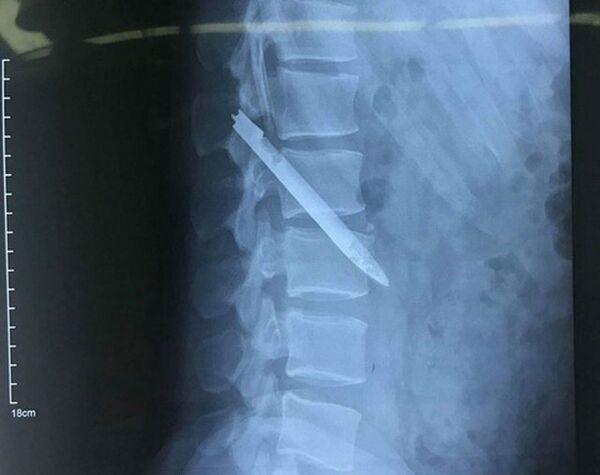

Trước đó, ngày 9-4, trong lúc đá bóng, anh Nam thấy lưng đau dữ dội nên đến Bệnh viện hữu nghị đa khoa tỉnh Nghệ An kiểm tra. Tiến hành chụp X quang, các bác sĩ bất ngờ phát hiện có dị vật bằng kim khí gần vùng cột sống thắt lưng của anh Nam.

Qua kiểm tra, các bác sĩ xác định dị vật là một lưỡi dao dài 13 cm. Lúc đầu anh Nam khá bất ngờ khi nghe các bác sĩ thông báo, tuy nhiên sau đó anh nhớ lại vào tháng 3-2007, khi đang công tác tại Công an huyện Thanh Chương (Nghệ An), trong lúc truy bắt một đối tượng truy nã, anh Nam bị đối tượng đâm nhiều nhát vào đầu, lưng, chảy nhiều máu phải nhập viện cấp cứu. Sau khoảng 1 tháng điều trị, chiến sĩ cảnh sát Nam xuất viện. Cũng theo anh Nam, sau khi bị thương, thỉnh thoảng anh vẫn thấy hiện tượng đau ở vùng lưng, nhưng không đi khám kiểm tra.

Sau khi thăm khám, ngày 17-4, các bác sĩ khoa Phẫu thuật Thần kinh cột sống, Bệnh viện hữu nghị đa khoa Nghệ An đã thực hiện ca phẫu thuật lấy ra lưỡi dao nằm chéo vùng cột sống thắt lưng của bệnh nhân Nam.

Theo nhận định của các bác sĩ, lưỡi dao dài 13 cm đã hoen gỉ lại nằm ở vị trí nguy hiểm, sát động mạch chủ bụng, nếu bệnh nhân vận động mạnh có thể khiến lưỡi dao di chuyển gây tổn thương mạch máu, ảnh hưởng đến tính mạng chiến sĩ công an.